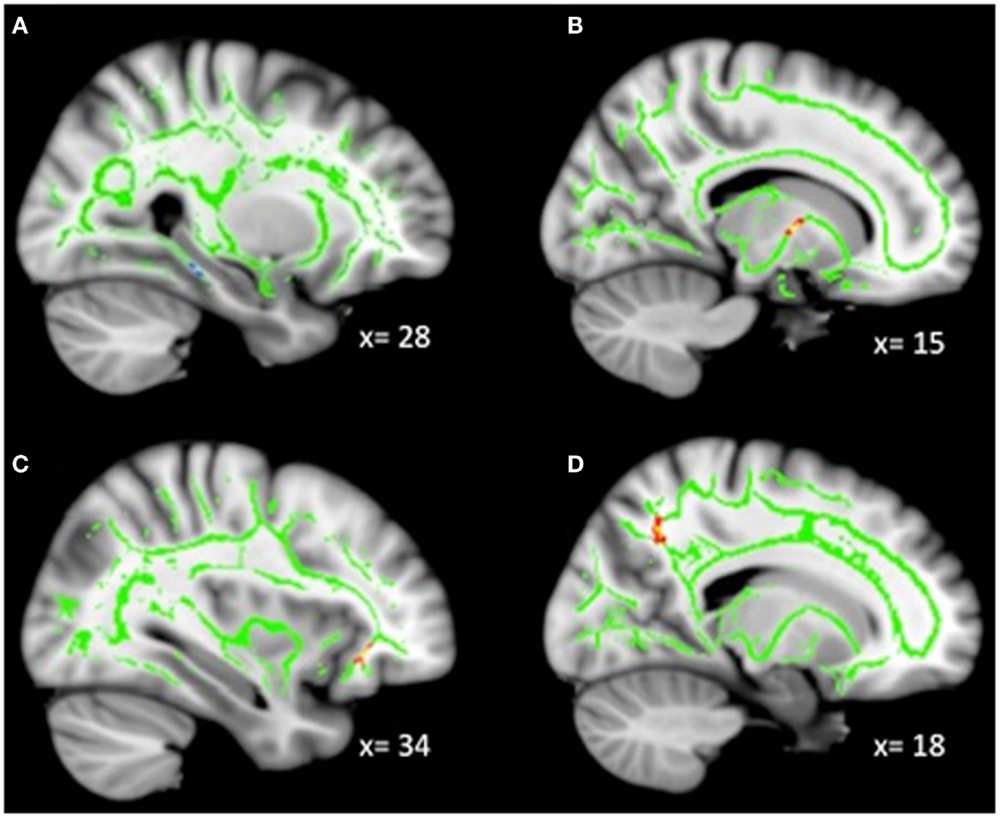

Analyses revealed a total of 14 uncorrected clusters, with 2 overlapping clusters (Table 5, Figure 4). As irritability increased, FA decreased in clusters in the sagittal stratum and IFOF, while MD increased in the same sagittal stratum cluster as well as in clusters in the ACR, SLF, and IFOF. For RD, positive correlations with irritability were evident in the same sagittal stratum cluster, the anterior limb of the internal capsule, and the SLF. Positive correlations were also found between AD and irritability in the same ACR cluster as the MD analysis as well as in the IFOF, the corticospinal tract, and the SLF.

Figure 4. Decreased WM integrity as irritability increased in the (A) sagittal stratum in the IT; (B) IFOF near the MFG. Key: IT, inferior temporal cortex; IFOF, inferior-fronto-occipital fasciculus; MFG, medial frontal gyrus.